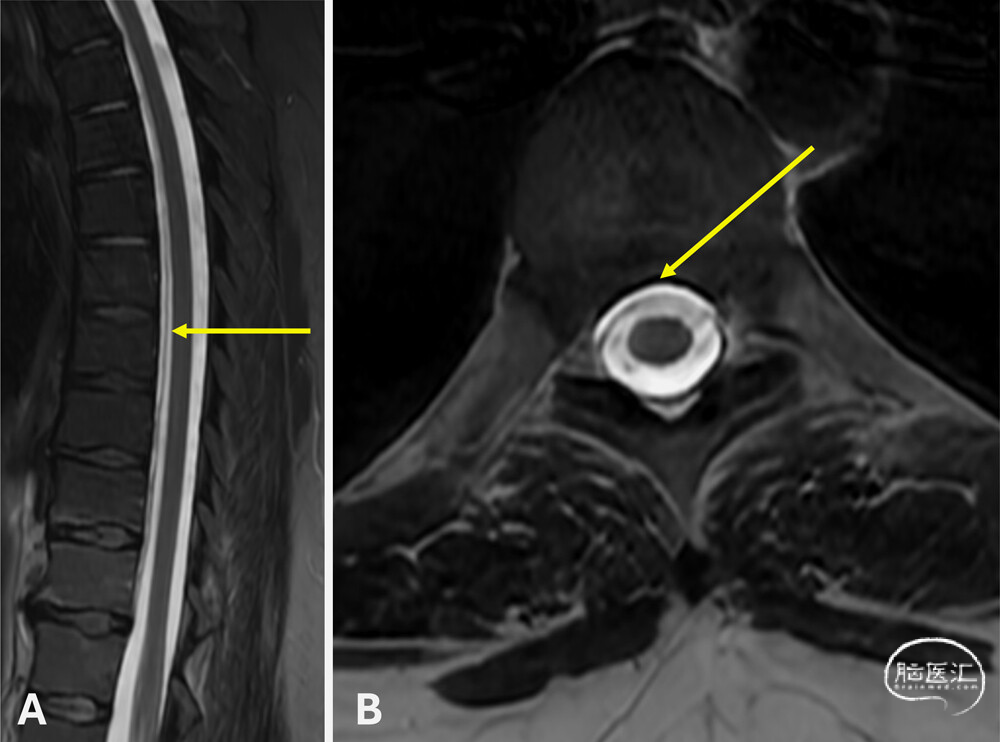

● 首次头颅非增强MRI显示符合颅内低压的影像学表现(图1)。因患者当时妊娠34周,暂缓CTM检查,由麻醉科医师在无影像引导下为其实施了非靶向腰椎硬膜外血贴治疗,术后症状完全缓解。6个月后,患者因症状复发再次就诊。复查增强头颅MRI仍提示颅内低压表现,并新增硬脑膜弥漫性强化(图2)。全脊柱MRI显示腹侧硬膜外脑脊液信号积聚,高度提示1型脑脊液漏(图3)。CTM证实存在T4至T11节段腹侧硬膜外造影剂积聚,但未能明确漏口位置。

图3:脊柱T2加权MRI图像,示腹侧硬膜外积液(箭头所示)。

1.dCTM定位漏口:最初由尾侧向头侧扫描,未见造影剂立即外渗,提示不存在高流量漏。随后由头侧向尾侧扫描时,在T10–11节段中线偏右侧发现一处细微的腹侧造影剂聚集(图4),提示存在硬膜缺损及脑脊液漏位置。延迟仰卧位扫描证实,边界清晰的腹侧硬膜外积液从T6–7延伸至T10–11,与既往检查结果一致。鉴于患者症状持续存在且已明确缺损位置,遂行开放性手术修补。

图4:动态CT脊髓造影显示,T10–11节段中线偏右侧可见微量硬膜外造影剂积聚(箭头所示)。